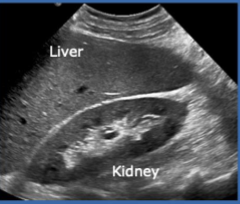

Echogenicity of this

isoechoic

Kidney = hypoechoic to liver

Liver = hyperechoic to kidney